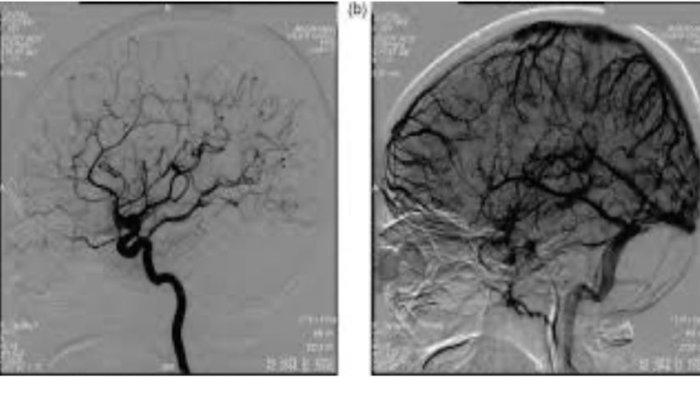

Digital Substraction Angiography (DSA) bertujuan untuk melihat dan mendeteksi masalah pada pembuluh darah yang ada di dalam atau yang menuju otak.

Ia pun diketahui menjalani tindakan Angiografi Otak atau Digital Substraction Angiography (DSA) di Mayapada Hospital Bandung untuk melihat dan mendeteksi masalah pada pembuluh darah yang ada di dalam atau yang menuju otak.

Dari hasil DSA, akhirnya diketahui bahwa keluhan pasien disebabkan oleh thrombosis vena cerebral, yakni adanya penyumbatan pada pembuluh darah vena di otak.

Menanggapi kasus tersebut, dr. Dedy Kurniawan, SpN (K), FINA sebagai Spesialis Neurologi Konsultan Neurointervensi Mayapada Hospital Surabaya menjelaskan, “DSA adalah prosedur diagnostik untuk melihat gambaran pembuluh darah otak, leher dan tulang belakang. Dengan tindakan DSA ini kita bisa melihat masalah apa yang terjadi di dalam pembuluh darah otak, leher dan tulang belakang."

"Apakah ada penyempitan di pembuluh darah arteri atau vena, penggelembungan pembuluh darah (aneurisma), malformasi pembuluh darah, dapat juga melihat lokasi dan derajat penyumbatan, berguna pula untuk mengevaluasi aliran pembuluh darah, dan membantu dokter untuk memetakan terapi yang sesuai dengan kelainan yang dialami pasien.”